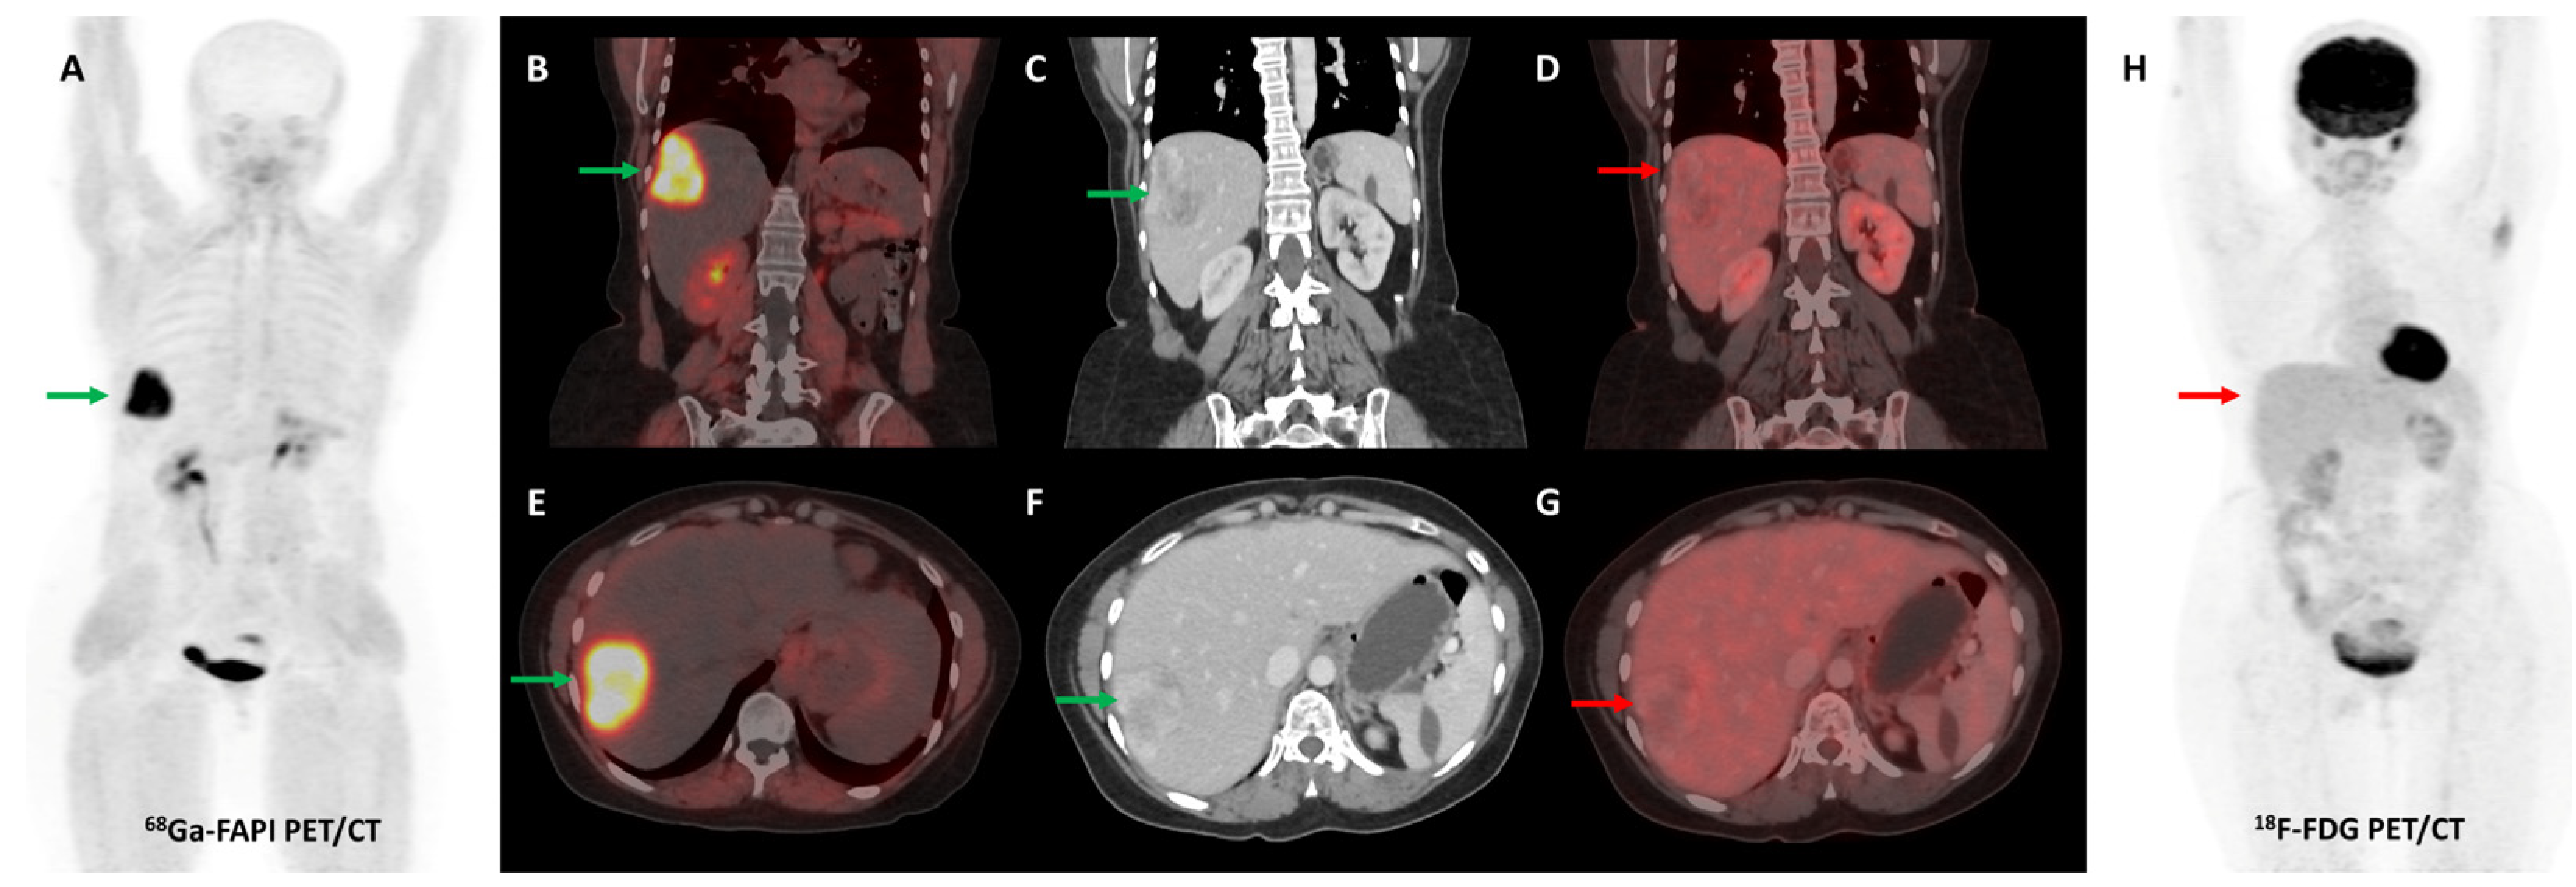

- Guo, W.; Pang, Y.; Yao, L.; Zhao, L.; Fan, C.; Ke, J.; Guo, P.; Hao, B.; Fu, H.; Xie, C.; et al. Imaging Fibroblast Activation Protein in Liver Cancer: A Single-Center Post Hoc Retrospective Analysis to Compare [68Ga]Ga-FAPI-04 PET/CT versus MRI and [18F]-FDG PET/CT. Eur. J. Nucl. Med. Mol. Imaging 2021, 48, 1604–1617. [Google Scholar] [CrossRef]

- Zhang, J.; He, Q.; Jiang, S.; Li, M.; Xue, H.; Zhang, D.; Li, S.; Peng, H.; Liang, J.; Liu, Z.; et al. [18F]FAPI PET/CT in the Evaluation of Focal Liver Lesions with [18F]FDG Non-Avidity. Eur. J. Nucl. Med. Mol. Imaging 2023, 50, 937–950. [Google Scholar] [CrossRef]